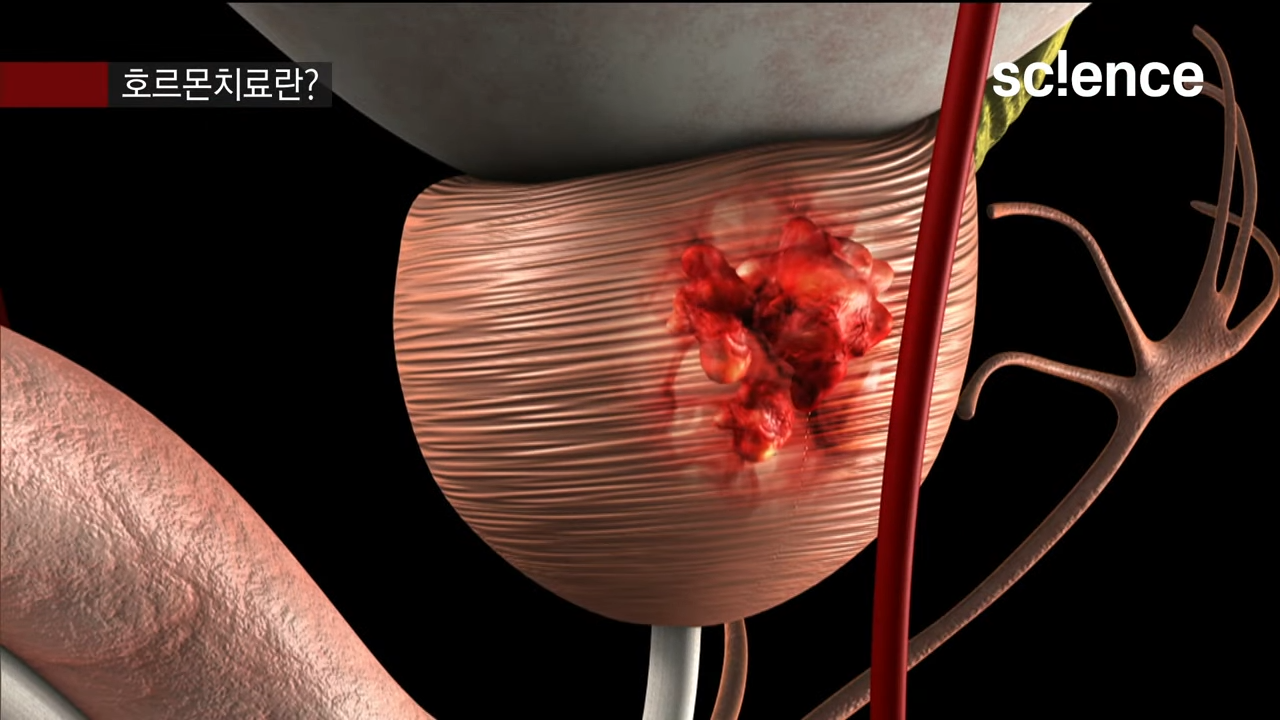

EBS 컬렉션 사이어스 - 유튜브 영상

명의가 알려주는 전립선암